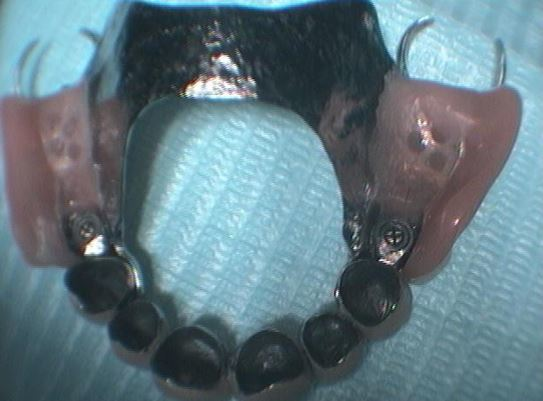

Στο ιατρειο μας κάθε χειρουργικο οδοντιατρικο περιστατικο καταγραφεται σε ολες του τις φασεις χρησιμοποιωντας μια συγχρονη ενδοστοματικη καμερα τελευταιας τεχνολογιας.Με τον τροπο αυτό διατηρουμε ένα πληρες αρχειο τοσο της αρχικης οσο και της τελικης καταστασης του ασθενους μας οσο και της εξελιξης της θεραπειας.Στο ιστορικο μας διαθετουμε ένα μεγαλο φωτογραφικο υλικο από οσα περιστατικα ελαβαν χωρα στο ιατρειο μας και είναι στη διαθεση σας ανα πασα στιγμη.Το αρχειακο μας υλικο θα ανανεωνεται συχνα με καινουργια περιστατικα. Στην παρουσα σελιδα μπορειτε να επισκεφτειτε μερικα από αυτα